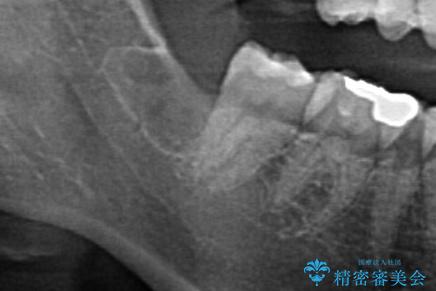

- 親知らずの抜歯を希望された患者様です。

CTを撮り下顎の神経が近くない事を確認し抜歯を行いました。